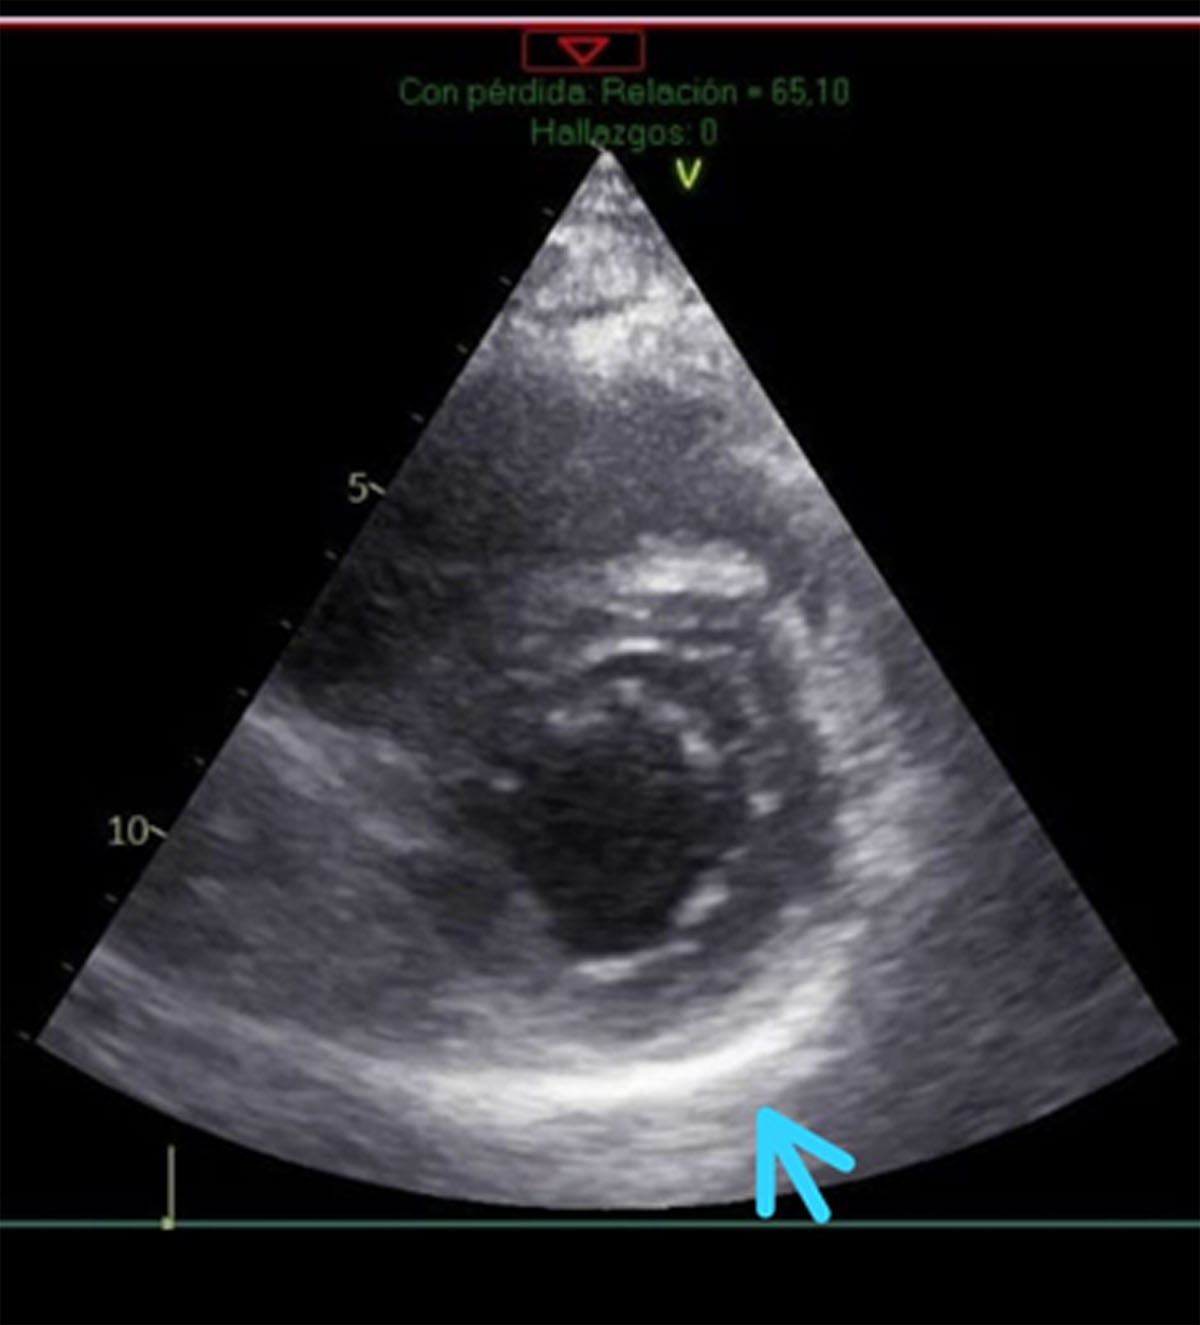

Simultaneously, a transthoracic echocardiogram was performed, revealing normal systolic function in both ventricles. The left ventricular ejection fraction (LVEF), assessed using Simpson’s method, was 66%, and the diastolic function was preserved. Longitudinal deformation was –19.8% with a minor decrease in the deformation affecting the basal and medial inferoseptal segment. Finally, the parietal pericardium was found enlarged and diffusely hyperechogenic, suggesting an inflammatory process at that level (Figure 2).

Figure 2

Echocardiogram of the short axis with thickening of the parietal pericardium.